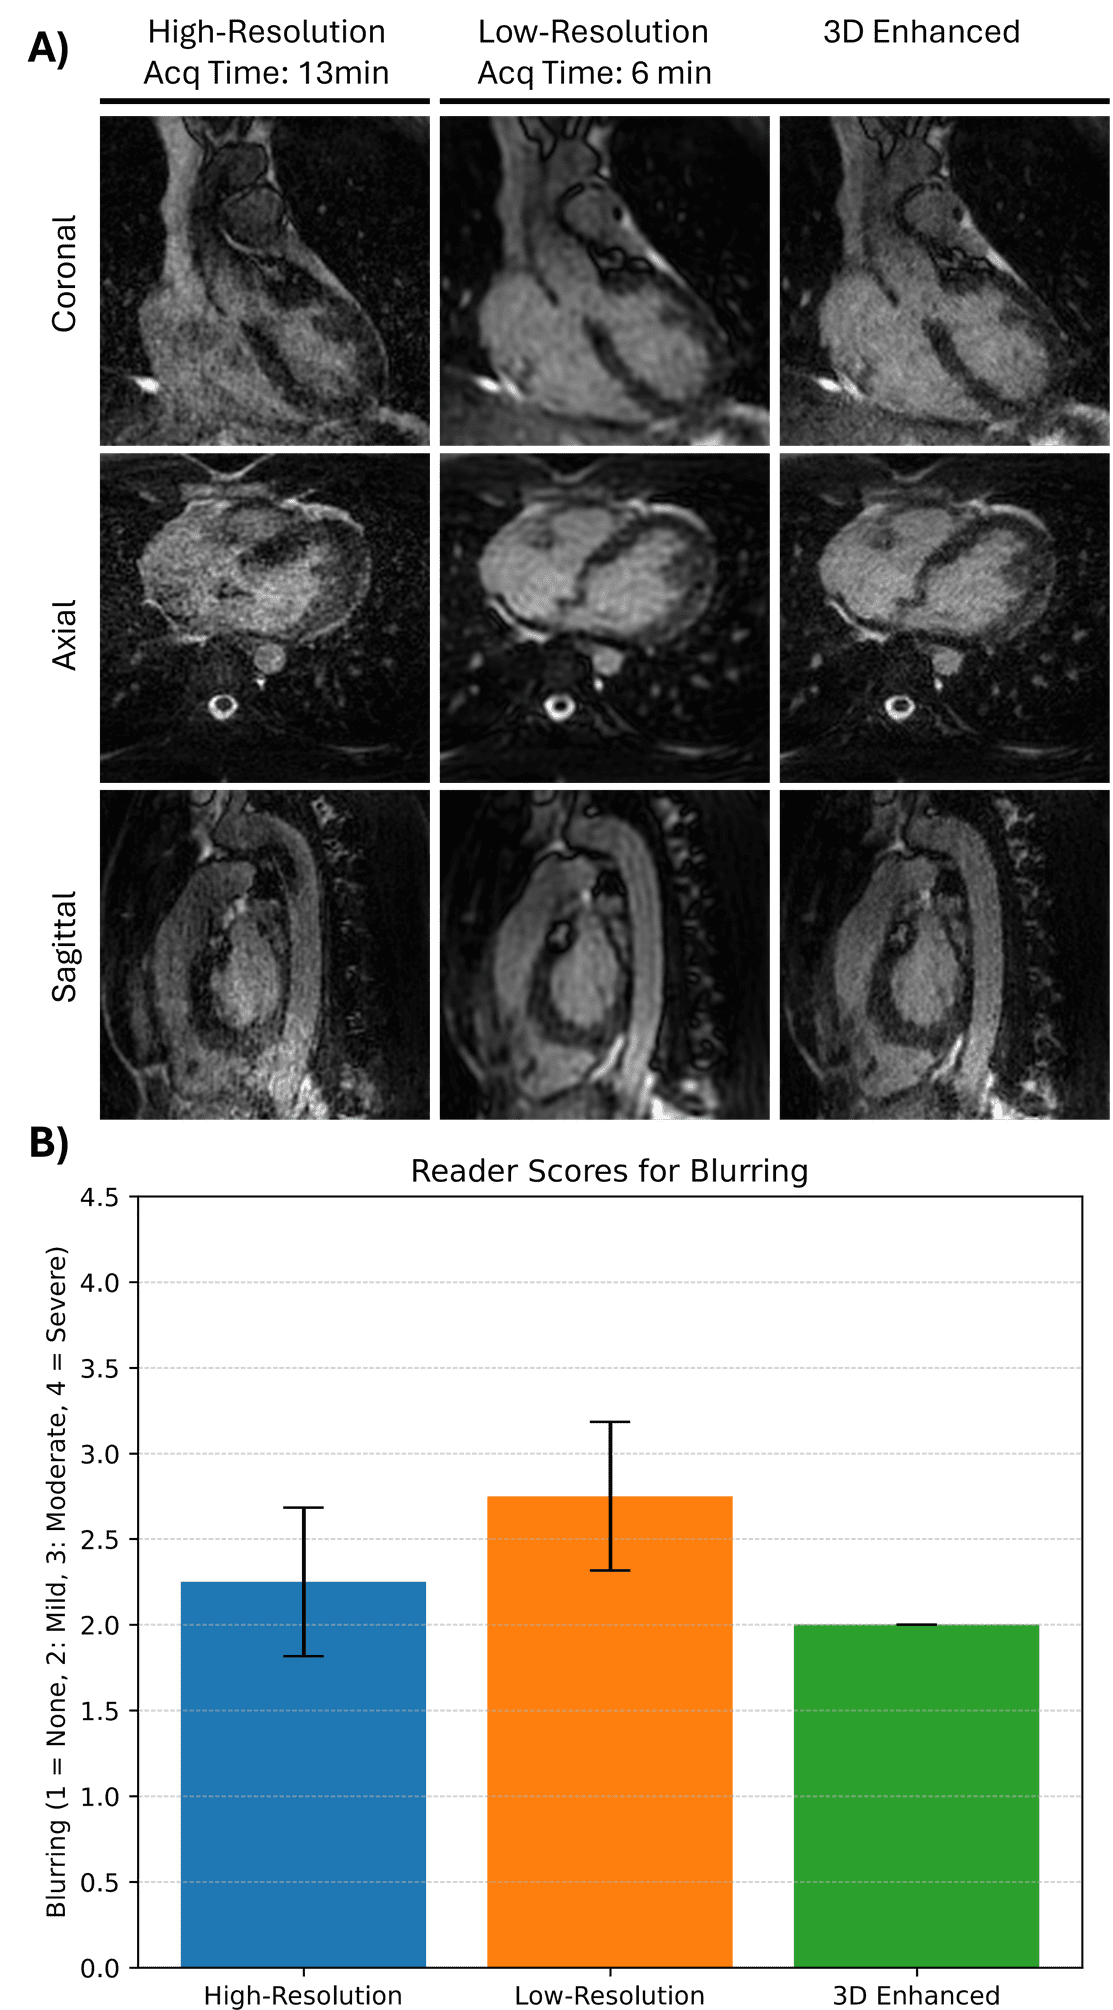

Figure 3: Prospective evaluation of the super-resolution model on low-field 0.6T free-running cardiac MRI acquisitions. (A) Representative axial, sagittal and coronal slices from a volunteer scanned with both high-resolution and low-resolution protocols. Low-resolution scans were acquired in approximately half the scan time (6:31 min vs. 13:08 min). 3D-enhanced images generated from the low-resolution inputs show clear visual improvements, with structural details and myocardial borders more closely resembling the high-resolution reference. (B) Results of a blind reader study across four prospective subjects. Images were scored using a 4-point Likert scale (1 = no blurring, 4 = severe blurring). 3D-enhanced images achieved a mean score of 2.0, showing improvement over low-resolution (2.75) and closer to high-resolution (2.25)..png)